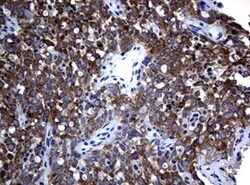

- Immunohistochemical staining of paraffin-embedded human ALK-positive lung cancer tissue using anti-ALK mouse monoclonal antibody. (TA801287, 1:100 for 30 min at RT; heat-induced epitope retrieval by TEE, pH9.0)